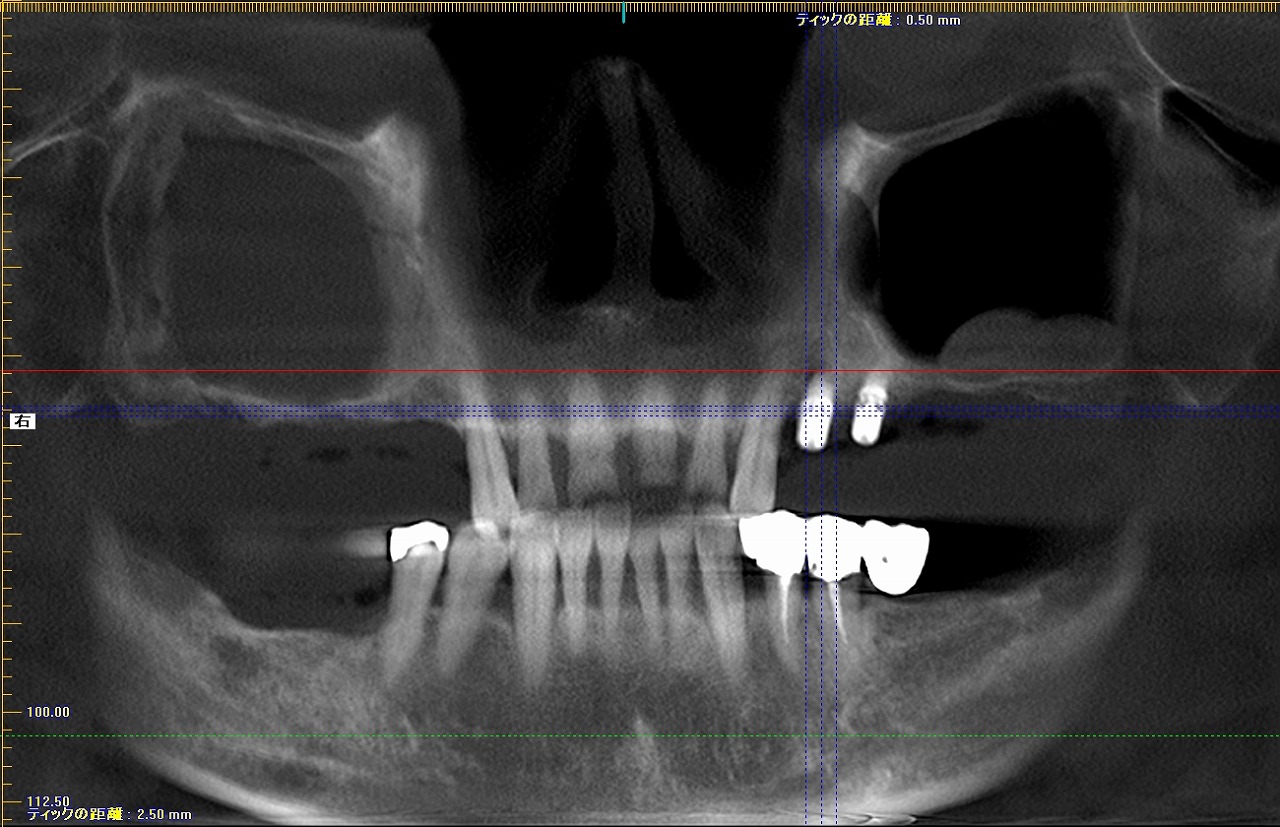

術後のパノラマになります